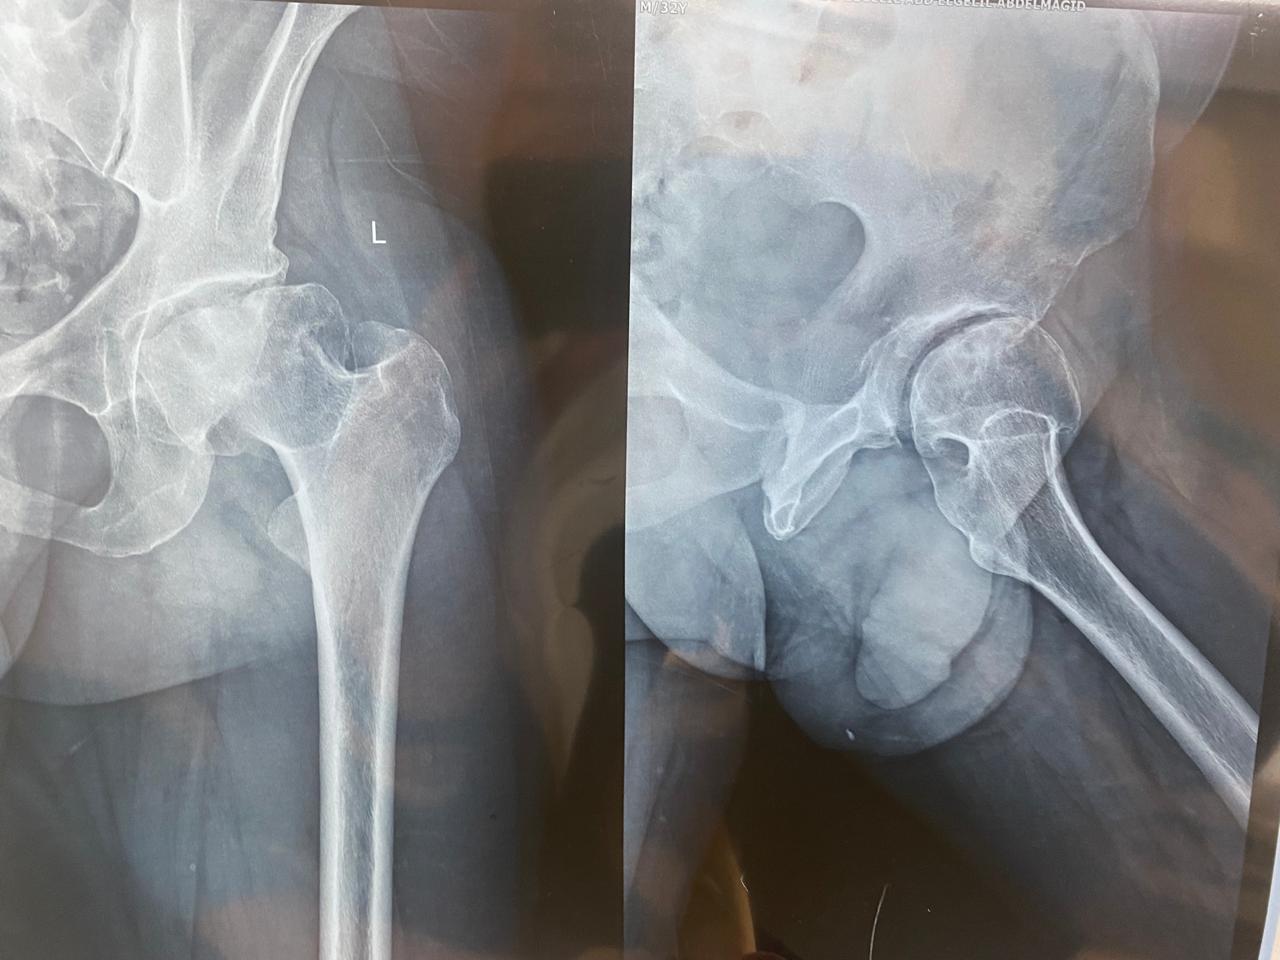

٣٠ عاما

يعاني من تاكل شديد منذ الطفولة في مفصل الحوض الأيسر.